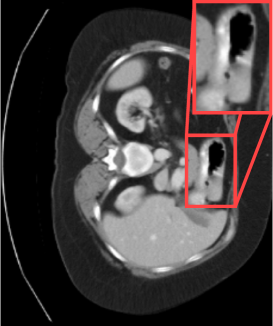

\bmvaHangBoxRefer to caption \bmvaHangBoxRefer to caption

(a) (b)

Figure 1: Medical imaging drawbacks.

This is because inappropriate normalization can occlude organs, as illustrated in Fig.1 (a). Additionally, clinicians can have different opinions in labeling[Alpert and Hillman(2004), Monteiro et al.(2020)Monteiro, Le Folgoc, Coelho de Castro, Pawlowski, Marques, Kamnitsas, van der Wilk, and Glocker, Becker et al.(2019)Becker, Chaitanya, Schawkat, Muehlematter, Hötker, Konukoglu, and Donati, Joskowicz et al.(2019)Joskowicz, Cohen, Caplan, and Sosna]. Due to this, ground truths are not determinstic, and it may be difficult to obtain detailed representations of organ or lesion labels. Inaccurate manual labeling can further increase the complexity of organ segmentation, as shown in Fig.1 (b). We address intrinsic challenges in medical images with an architecture that combines the advantages of the adaptive and resilient Swin Transformer encoder[Liu et al.(2021)Liu, Lin, Cao, Hu, Wei, Zhang, Lin, and Guo] with the efficient decoder in UNet[Ronneberger et al.(2015)Ronneberger, Fischer, and Brox]. We break away from the conventional Denoising U-Net[Rombach et al.(2022)Rombach, Blattmann, Lorenz, Esser, and Ommer] structure because we need a model that captures a global contextual representation and can handle the various medical imaging data. In addition, we introduce three approaches to improve the segmentation process further. First, distance-aware label smoothing[Yu et al.(2017)Yu, Liu, Gong, Zhang, Batmanghelich, and Tao, Zhang et al.(2023)Zhang, Zheng, Shi, et al., Felfeliyan et al.(2023)Felfeliyan, Hareendranathan, Kuntze, Wichuk, Forkert, Jaremko, and Ronsky] is a guidance mechanism that recognizes anatomical locations in the medical image and smoothes labels by calculating location-based distances. Second, reverse boundary attention captures areas of subtle and ambiguous boundaries. This component contributes to more precise and accurate segmentation by explicitly directing the model attention to edges[Wang et al.(2022)Wang, Chen, Ji, Fan, and Li, Lee et al.(2020)Lee, Kim, Lee, Kim, and Ro], especially in the regions that have not been manually labeled. Third, self-supervised learning[Alzubaidi et al.(2020)Alzubaidi, Fadhel, Al-Shamma, Zhang, Santamaría, Duan, and R. Oleiwi, Ghesu et al.(2022)Ghesu, Georgescu, Mansoor, Yoo, Neumann, Patel, Vishwanath, Balter, Cao, Grbic, and Comaniciu, Shurrab and Duwairi(2022)] allows complex features of organs to capture meaningful representations from input images in a scenario of insufficient data. We reduce reliance on labeled data and improve model adaptability to diverse and complex features of medical images. Our proposed method demonstrates generalizability beyond medical images when we evaluate it with a different domain task that can utilize morphological information. Therefore, our contribution is summarized as follows.

we propose a k𝑘kitalic_k-neighbor label smoothing method that leverages the relative positions of organs for distance-aware smoothing of the labels of k𝑘kitalic_k neighbors for a given class or organ. In a multi-class (k>2𝑘2k>2italic_k > 2) situation, such as in this case, there is an advantage if there is a positional relationship between them. The positional relationship refers to the relative positional relationship of organs anatomically. As shown in Fig. 1 (b), the liver(\star) is close to the gall bladder(\blacktriangle) but relatively far from the left kidney(\blacksquare). We provided semantic information to the model based on which body structure would match this prior knowledge. The equation of k-neighbor label smoothing (kNLS𝑘𝑁𝐿𝑆k-NLSitalic_k - italic_N italic_L italic_S) is: